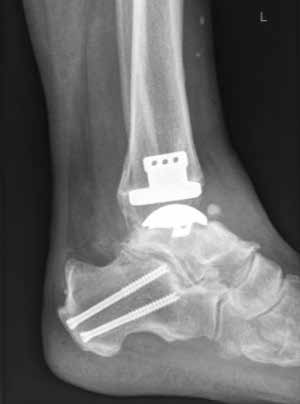

Endoprothetik des OSG

Die Indikation zur endoprothetischen Versorgung einer OSG-Arthrose ist gründlich zu stellen. Darunter fällt die schwere Arthrose jeglicher Ätiologie mit täglich intensiven Schmerzen, hochgradigem Gelenkfunktionsverlust und Gelenkdestruktion. Voraussetzungen sind eine gute Knochenqualität sowie mittleres Alter ohne schwere systemische Vorerkrankungen. Auch bei der Implantation von Endoprothesen des oberen Sprunggelenkes ist es wichtig, bestehende Achsfehlstellungen entweder in gleicher Sitzung oder zuvor zu korrigieren. Sofern nach Achskorrektur die Versorgung mittels einer Endoprothese noch notwendig ist, soll damit die Funktionsfähigkeit des Gelenks, eine Schmerzeliminierung und eine Verbesserung der Lebensqualität erreicht werden (Abb. 6). Kontraindikationen sind neben den bereits oben genannten: bestehende Osteonekrosen, periphere arterielle Verschlusskrankheit, periphere Neuropathie, bestehende oder stattgehabte Gelenkinfektion und schwere Bandinstabilität 56.

Im Vergleich zur Endoprothetik des Hüft- und Kniegelenks bestehen höhere Komplikationsraten bei der Endoprothese des Sprunggelenks. Intraoperativ sind dies meist operationstechnische Komplikationen bei der Osteotomie der Malleoli, beim Sägen oder beim Positionieren der Prothesenkomponenten 57. Postoperativ sind dies vornehmlich Wunddehiszenzen und Infektionen 58, während im Langzeitergebnis aseptische Prothesenlockerung, periprothetische Stressfrakturen und Retraktion der Gelenkkapsel sowie der periartikulären Weichteile auftreten 59.